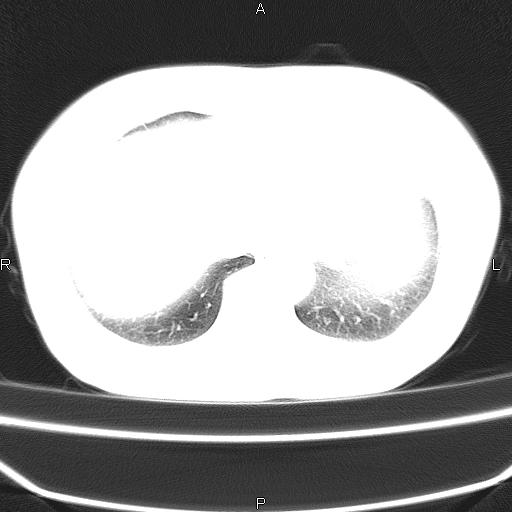

患者,女,66岁。健康体检胸部透视发现右上肺片状阴影。既往无不适,患者自诉三个月前曾有低热病史体温37.5左右一周。用药后缓解。至今无其它不适。请老师们指导指导。

考虑:右肺上叶周围型肺癌(分叶状肿块+砂粒状钙化+胸膜尾征)。

病灶见明显分叶、大小较大(大于3cm?),老年人,多考虑:肺癌,建议穿刺活检。

典型的中心型肺癌,尖段支气管阻塞。

右肺上叶周围型肺癌可能性大。

考虑:右肺上叶周围型肺癌